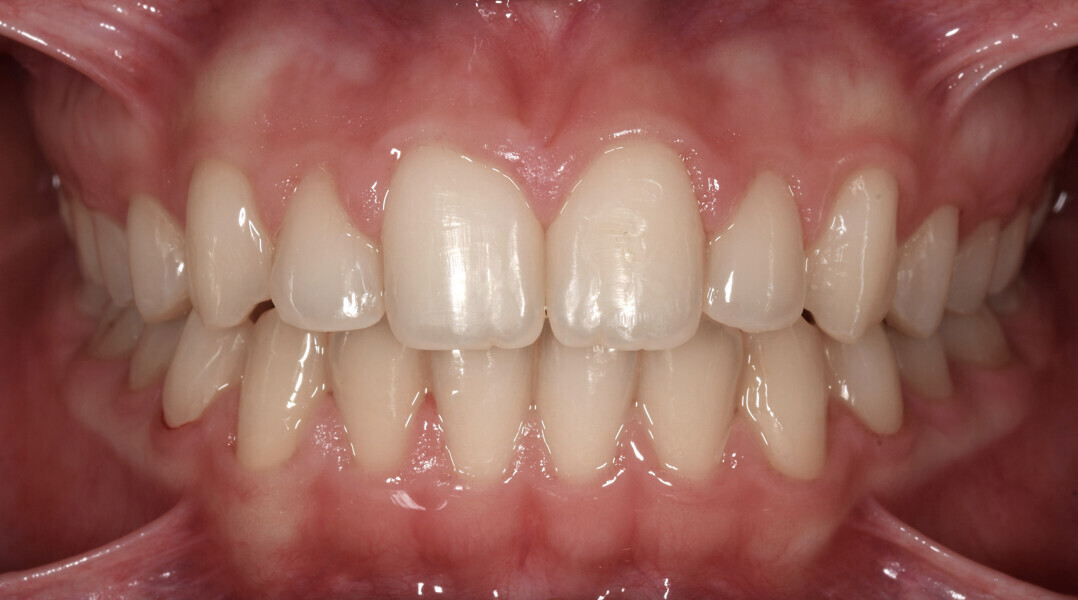

Treatment result

Final results were achieved with 42 aligners that were changed weekly (10.5 months of treatment), leading to a very aesthetic final outcome (Figs. 16–25), pleasing to the patient and her parents. All details in the anterior aesthetic zone were addressed, and it is those corrections that gave the patient the smile she desired: a smile line following the lower lip with attractive anterior buccolingual inclination and ideal gingival display according to her age.

Fig. 18: Final intra-oral photograph.

Fig. 19: Final intra-oral photograph.

Fig. 20: Final intra-oral photograph.

Fig. 21: Final intra-oral photograph.

Fig. 22: Final intra-oral photograph.

Fig. 23: Final intra-oral photograph.